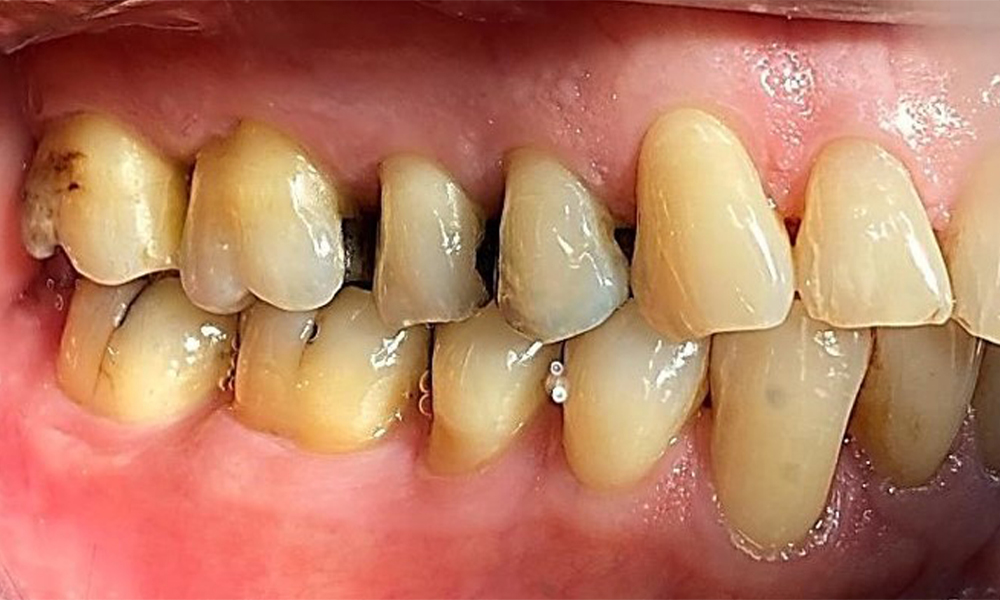

Left lateral view including the recessions.

Fig. 4 Left lateral view including the recessions. © Dr R. Krapf

The patient has stage II, grade B periodontitis (5). At 1 to 3 mm, the clinical probing depths were within the physiological range. Localized probing depths of 5 mm were observed on the mesiopalatal aspects on both 17 and 27. There are generalized recessions of 1–3 mm with partial loss of the interdental papillae (Fig. 2, Fig. 3, Fig. 4)